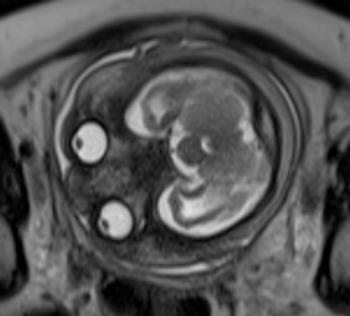

In a third study, ultrasound and fetal MRI were performed on pregnant patients with Zika virus infection at different gestational ages. Once the babies were born, they underwent ultrasound, CT and MRI. The researchers then created 3-D virtual and physical models of the skulls. More than half the babies had microcephaly, brain calcifications and loss of brain tissue volume, along with other structural changes.

"The emergence of Zika virus in the Americas has coincided with increased reports of babies born with microcephaly," said study author Heron Werner Jr., M.D., Ph.D., from the Department of Radiology at Clínica de Diagnóstico por Imagem. "An early diagnosis may help in treating these babies after birth. Moreover, the knowledge of abnormalities present in the central nervous system may give hints about the pathophysiology of the disease."